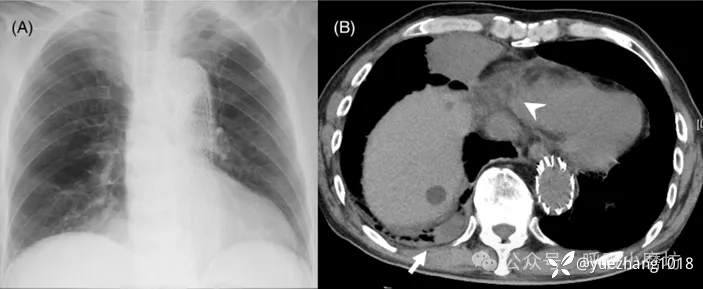

80岁男性患者,因突发胸痛、高热(T 40.1°C)和低氧血症就诊。

实验室检查提示感染(WBC 12,050/µL,CRP 6.46 mg/dL)。

胸片显示右下肺野团块影(图4A)。胸部CT证实该团块为坏死的纵隔脂肪组织,并合并邻近肺叶的吸入性肺炎(图4B)。

图4A 入院时胸部X线片示右下肺野团块影;4B CT显示肿块和坏死的心包外脂肪(箭),并伴有吸入性肺炎(箭头)

经抗生素及对症治疗,患者感染控制。

2个月后随访影像显示肺部炎症吸收,原脂肪病灶亦显著缩小(图4C, D)。

图4C, 4D 2个月后复查的胸部X线片和胸部CT